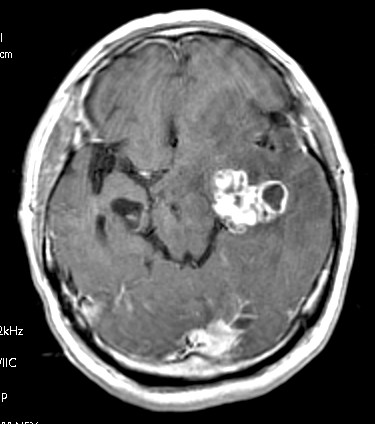

転移性脳腫瘍(腎転移) CE_T1W1_axi_1 CE_T1W1_axi_2